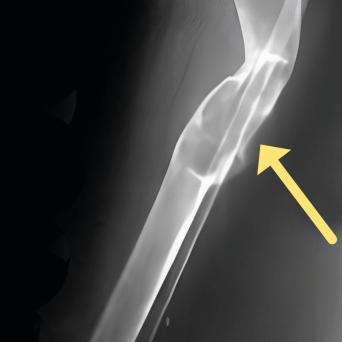

Lacertus fibrosus : à ne pas confondre avec le canal carpien !🎬

Le syndrome du lacertus fibrosus est une affection courante, mais encore largement méconnue. Souvent confondu avec le syndrome du canal carpien, son diagnostic est négligé ou posé tardivement, parfois après échec d’une chirurgie pour syndrome du canal carpien. Pourtant, certains signes sont caractéristiques et l’examen clinique permet de distinguer ces deux pathologies et d’orienter rapidement les patients. Flash interview du Dr Marc-Olivier Falcone, chirurgien orthopédiste et traumatologue, Paris.